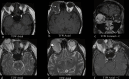

The lacrimal gland is a bilobed serous gland located in the superolateral aspect of the orbit. Lacrimal system pathologies can be broadly divided into pathologies of the lacrimal gland and those of the nasolacrimal drainage apparatus. These include distinct congenital, infectious, inflammatory, and benign, indeterminate, and malignant neoplastic lesions. Trauma and resultant fractures affecting lacrimal drainage apparatus is not part of this review; only non-traumatic diseases will be discussed. CT is the initial modality of choice because of its ability to delineate lacrimal system anatomy and demonstrate most lacrimal drainage system abnormalities and their extent. It also assesses bony architecture and characterizes any osseous changes. MRI is helpful in further characterizing these lesions and better assessing involvement of the surrounding soft tissue structures. In this pictorial review, we will review the anatomy of the lacrimal system, describe CT/MRI findings of the common and uncommon lacrimal system abnormalities and discuss relevance of imaging with regards to patient management.